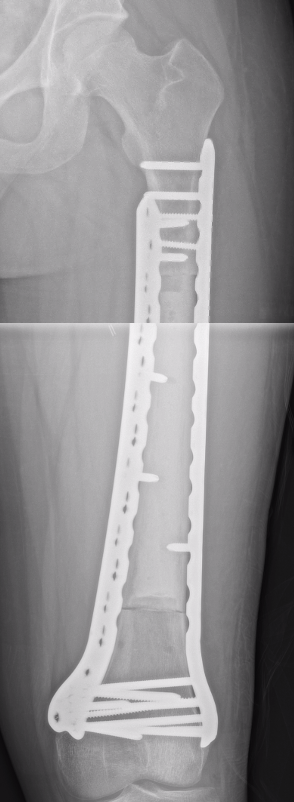

Wide Resection - limb salvage / amputation

2 cm margin of normal tissue if able

Assess histological response

Radiotherapy

Indications

- inadequate margins

- non resectable

- poor response to chemotherapy